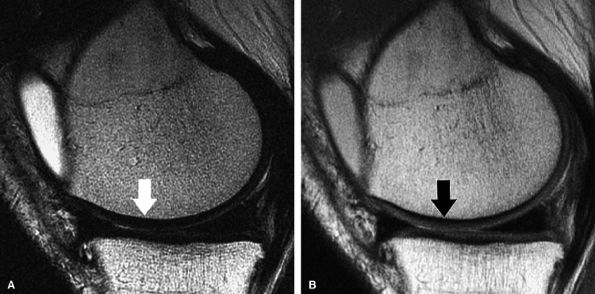

Heavily T2-weighted sequences, with echo times in excess of 80 msec, depict the cartilage as being relatively hypointense compared to high-signal-intensity fluid. It is important to remember, however, that because of the normal stratification of the extracellular matrix in cartilage, T2 values are shorter in the radial zone (closer to the subchondral plate) than in the transitional zone, where the collagen is more randomly oriented and T2 values are prolonged. This normal stratification can be perceived on appropriate cartilage-sensitive scans and provides insight into the cartilage ultrastructure (Fig. 7.3).

With longer echo times there is poor delineation between the basilar components of the cartilage and the subchondral plate. This may account for factitious thickening of the subchondral plate and thinning of the cartilage (see Fig. 7.3).

FIGURE 7.3 ● (A) Sagittal fast spin-echo MR image of the knee in a 39-year-old man performed on a high-field system (1.5 Tesla) demonstrates poor distinction between the subchondral plate and adjacent basilar components of cartilage at a TE of 110 msec (white arrow). (B) Corresponding image with all acquisition parameters held the same except for a moderate TE of 27.5 msec demonstrates improved cartilage–subchondral bone distinction (black arrow).